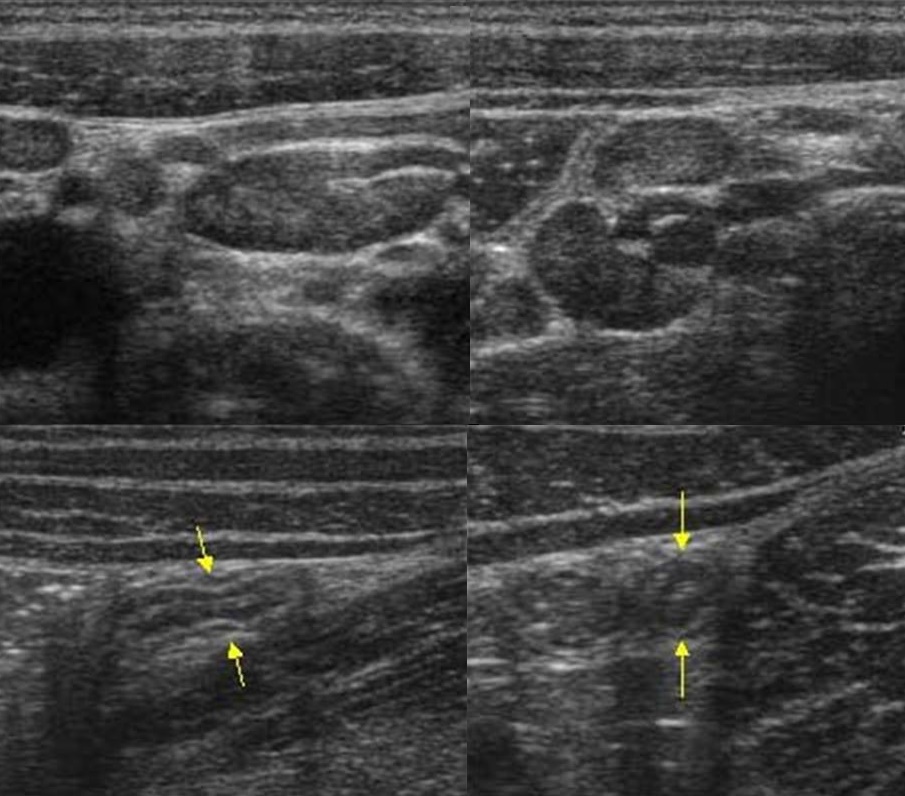

Мезентериальные лимфатические узлы: УЗИ и диагностика